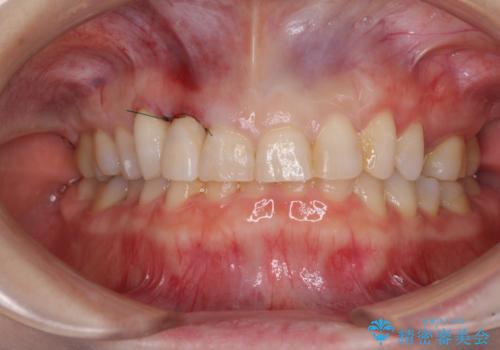

- 前歯のクラウン周りに歯肉が腫れていることを気にして来院された患者様です。

元々磨き残しによる歯肉の腫脹がありましたが、クラウンが歯肉深くに装着されていたため、特に腫脹が目立っていました。

仮歯に置き換えた際に歯周外科処置を行い、歯肉の腫脹が落ち着いたことを確認してオールセラミッククラウンにて補綴することとしました。

外科処置後の痛みを気にしていましたが、小規模の処置であったため、痛みを感じることはほとんどありませんでした。

気になっていた腫脹がなくなり、患者様には大変満足していただきました。